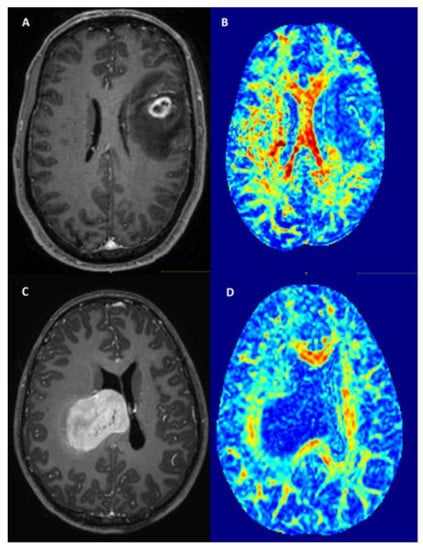

Patients with tumor location in the right cingulate gyrus (adj. p = 0.048) and in the right caudate nucleus (adj. p = 0.009) showed significantly less preoperative seizures (Table 3). Patients with tumors in the limbic system (including parahippocampal and hippocampal gyrus and cingulate gyrus) also showed significantly less preoperative seizures (p = 0.030) All other tumor locations were not associated with the occurrence of preoperative seizures. Figure 2 shows examples of a patient with a small tumor in the left frontal lobe presenting with seizures (A,B) and a patient with a large tumor in the right cingulate gyrus presenting without preoperative seizures (C,D).

Figure 2.

Examples of patients with (A) = T1-weighted imaging after contrast agent, (B) = Fractional anisotropy maps) and without (C,D) preoperative seizures.